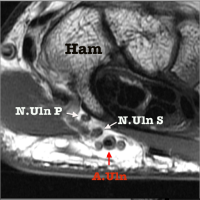

accompagnée en dedans, par le nerf ulnaire, elle passe dans le canal de Guyon

L’ Artère Ulnaire

oblique en bas et en dedans, elle gagne progressivement le bord médial du bras, puis elle descend verticalement jusqu’au pisiforme et devient oblique en dehors à la main.